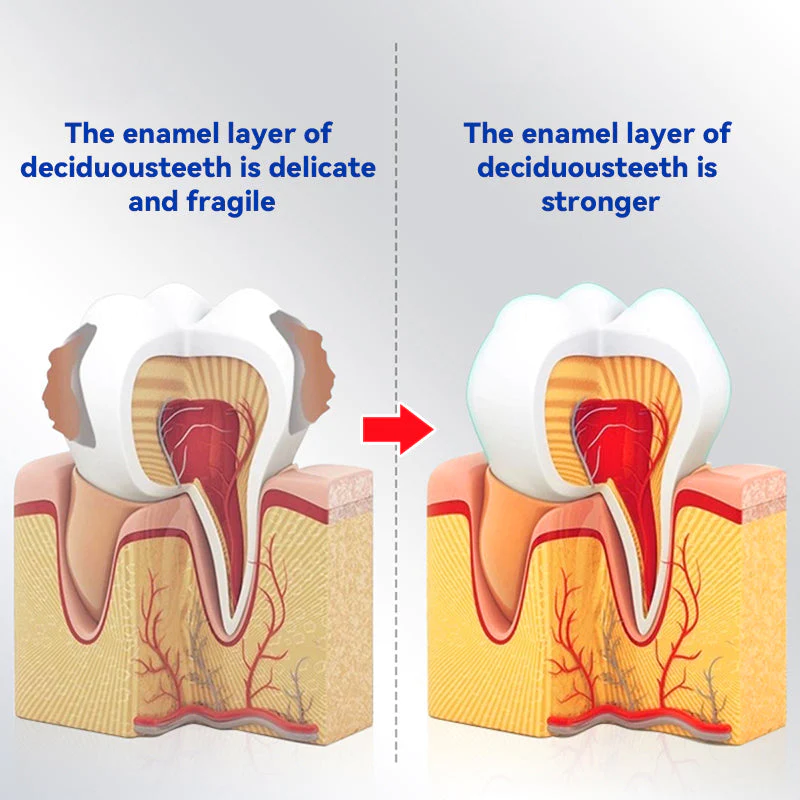

Oraliz anti-cavity toothpaste with mint scent utilizes a combination of bioactive silica, oral probiotics adp-1, and zinc citrate to protect against cavities, promote gum health, and freshen breath. Bioactive silica helps to strengthen tooth enamel, while oral probiotics adp-1 support a healthy oral microbiome. Zinc citrate helps to reduce plaque and neutralize bad breath. Regular use of this toothpaste can lead to improved overall oral health.

Bioactive Silica in Oraliz anti-cavity toothpaste is a superior ingredient compared to competitors. It has a lower abrasiveness index than many other toothpaste abrasives, which means it is less likely to cause enamel damage. It also has antibacterial properties that help reduce plaque and cavities, making it an excellent choice for maintaining healthy teeth and gums. Overall, Bioactive Silica provides superior cleaning and oral health benefits compared to other toothpaste ingredients.

A study published in the Journal of Dentistry in 2017 evaluated the effectiveness of Bioactive Silica-based toothpaste in remineralizing enamel and reducing the formation of caries lesions. The study found that Bioactive Silica-based toothpaste was effective in remineralizing enamel and reducing the formation of caries lesions in vitro.